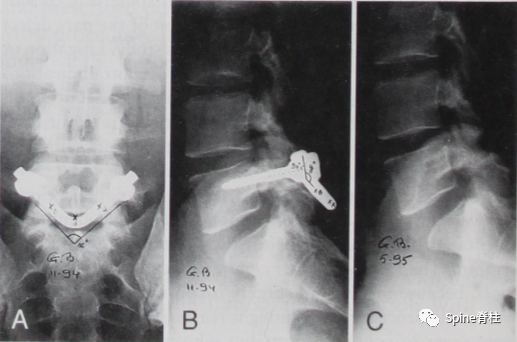

并建议保守治疗无效的青年战士A、B型腰椎峡部裂病例采用椎弓根螺钉固定,峡部自体髂骨原位植骨融合率高,效果好,C型战士峡部裂则宜采用后路椎间植骨融合椎弓根螺钉内固定术。

随着内固定的发展,既往峡部单纯修复植骨因融合率低、卧床时间长,现已很少应用。而植骨修复并节段固定有多种方法,包括Scott接线法、Buck螺钉法、Louis的蝶形板、钉钩技术(椎弓根螺钉和钩-棒系统)、U形棒等。从临床角度看,钉钩技术可以用刚性植入物固定断裂的峡部,并沿椎板方向施加作用力,有效稳定峡部,这对于达到更好的骨性愈合是至关重要的。理论上,此种方法更符合生物力学,对邻近节段影响小,但应把握好适应症,建议单纯腰椎峡部裂伴或不伴轻度滑脱患者可行植骨修复并节段固定。

1. 椎弓根螺钉-钉钩系统

PMID: 9199377